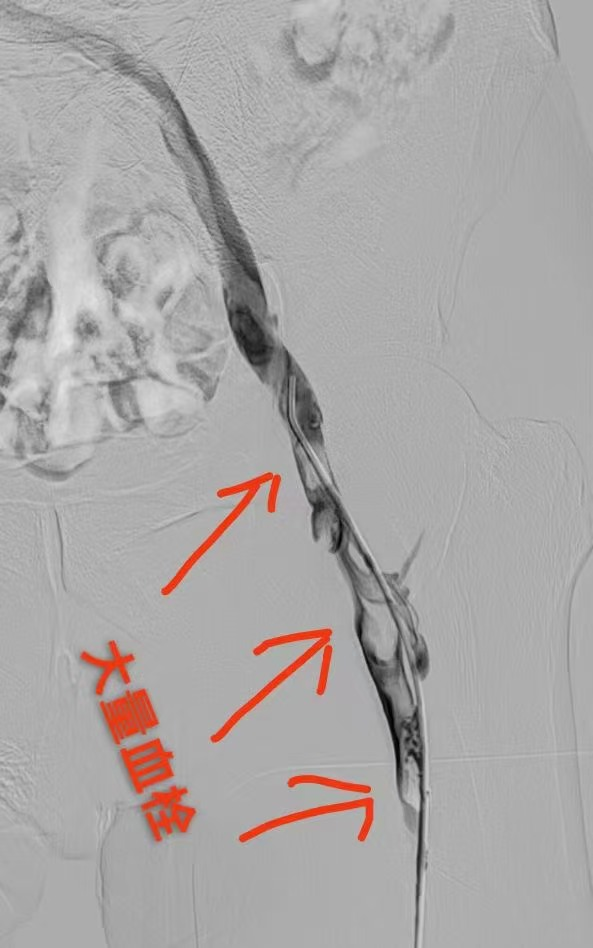

圖一為下肢血栓形成影像圖片 圖二為與圖一同部位經(jīng)過治療后血栓消失照片(圖片來源網(wǎng)絡,如有侵權聯(lián)系刪除)